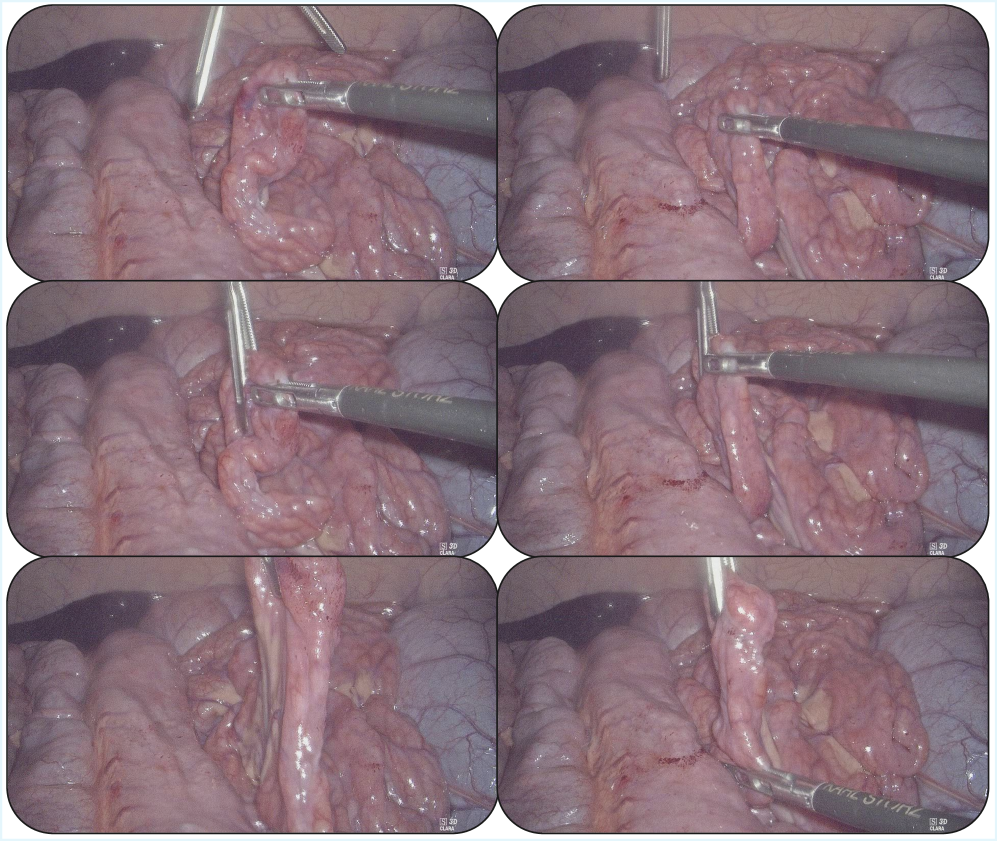

Despite advances in robotic manipulation, applying imitation learning to minimally-invasive surgery remains challenging due to limited data and the need for exceptional safety. This work, ‘MoE-ACT: Improving Surgical Imitation Learning Policies through Supervised Mixture-of-Experts’, introduces a supervised Mixture-of-Experts architecture for action transformer policies, enabling robust and data-efficient learning of surgical tasks from limited visual input. We demonstrate significant performance gains over state-of-the-art methods in collaborative surgical tasks-specifically, bowel grasping and retraction-and achieve zero-shot transfer to ex vivo porcine tissue. Could this approach pave the way for more adaptable and reliable surgical robots capable of assisting surgeons in complex procedures?

A novel surgical assistance system, leveraging the Mixture-of-Experts architecture, was successfully implemented during in vivo porcine surgery, marking a significant step toward real-world clinical application. This approach allows the system to dynamically select and combine specialized “expert” networks tailored to different tissue types and surgical conditions encountered during the procedure. The in vivo validation demonstrated the system’s ability to function reliably within the complex and unpredictable environment of live tissue, paving the way for future development of intelligent tools that can augment a surgeon’s capabilities. By effectively navigating the challenges of a live surgical setting, this research highlights the potential of advanced machine learning to improve surgical precision, efficiency, and ultimately, patient outcomes.

The system’s capacity for zero-shot transfer was powerfully demonstrated through an 80% success rate on ex vivo porcine tissue. This signifies the model’s ability to generalize learned features from training datasets – initially focused on distinct image sources – to a completely new biological context without any additional training or fine-tuning on porcine data. Such performance is critical for practical surgical applications, where acquiring extensive labeled datasets for every anatomical variation or surgical scenario is impractical. The successful transfer highlights the robustness of the learned representations and suggests a fundamental understanding of tissue characteristics, enabling reliable performance even when presented with previously unseen biological samples. This adaptability represents a significant step towards creating surgical assistance tools that can operate effectively in diverse and unpredictable clinical environments.